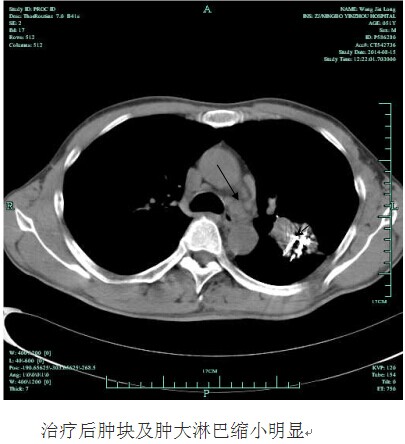

今年50岁家在我市江北区的王师傅,一个月前连续1周突然莫名发热,自行服了很多药都未见好转。由于体温一直徘徊在38.0左右,老王来到我院呼吸科就诊,门诊检查后,发现王师傅血红蛋白明显偏低,考虑贫血,当即将他收治入院。患者入院后,经胸X片等各项常规检查发现,王师傅左侧肺部有一巨大的阴影。进一步的胸部CT提示:首先考虑恶性肿瘤,且肿瘤巨大,有7X8CM大小,肿瘤内部已经发生溃烂坏死,同时远处的淋巴结已经转移。随后的肺活检证实王师傅得了肺腺癌。因为肿瘤已经晚期,错过了手术的机会,王师傅体质又偏弱,恐怕无法耐受化疗,全家人天天以泪洗面,王师傅更是已到精神崩溃边缘。针对患者的严重病情,为挽救其生命,呼吸科学科带头人俞万钧副院长和彭卫东主任,经多次组织科室讨论治疗方案,同时对患者病例通过远程网络会诊,和浙江省肿瘤医院的权威专家制订了放射性粒子碘125置入肿瘤的姑息治疗方案。手术在局麻下进行,其方法是首先在CT定位下确定粒子置入的位置,进定位针,深入肿瘤内部,沿定位针放置放射性粒子。手术非常顺利,术中王师傅一直保持清醒状态,术后3天,王师傅就出院了。昨日王师傅来我院复诊,除早已没有发热症状外,整个人精神状态非常好,和常人无异,胸部CT复查发现左肺的肿瘤已经缩小近一半,更为不可思议的是,王师傅左胸肿大转移的淋巴结也变小了。据悉,接下去呼吸科将为王师傅制定下一步诊疗计划,以抑制肿瘤的再次增长。